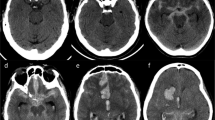

DCI is an exclusion diagnosis and can only be confirmed by imaging. Multimodal CT is frequently applied as a differential diagnostic tool at the moment of delayed neurological deterioration. NCCT is useful to exclude other causes of delayed neurological deterioration, such as hydrocephalus, rebleeding, or cerebral oedema. CTA is a good non-invasive alternative to DSA for diagnosing ACV (Figure 5A) [32]. Both techniques have a high degree of correlation for proximal ACV (agreement between 92 and 95%) [35],[36]. However, the ability to monitor regional cerebral blood flow (CBF) and to assess global and regional cerebral perfusion is the main recent advance in DCI monitoring. Computed tomography perfusion (CTP) can be performed as a component of multimodal CT scanning (Figure 5B, C). The combination of CTA/CTP is more sensitive for ACV than TCD [33] and DSA [37].

Multimodal computed tomography. (A) Computed tomography (CT) angiography (coronal plane) shows severe angiographic vasospasm in the left middle cerebral artery (MCA; red arrow). (B) CT perfusion displays increased mean transit time (increased shades of red in the left hemisphere) due to MCA vasospasm. (C) Same patient, CT perfusion repeated after 48 hours of haemodynamic augmentation, which shows resolution of perfusion changes. (D) Noncontrast computed tomography (NCCT) showing the measurement of bicaudate index (A/B) as proposed by van Gijn and colleagues [98]. (E) NCCT shows large volume of intraventricular haemorrhage. The tip of the bilateral external ventriculostomy drains can be seen in the anterior horn of the lateral ventricles (blue arrows). (F) NCCT quality severely compromised by artefacts generated by the metallic colis.

Two high-quality meta-analyses that were recently published included 15 studies with 915 patients [38],[39]. The first meta-analysis included studies that defined DCI as: clinical deterioration not explained by other causes; cerebral infarction on follow-up CT or MRI; and functional disability related to DCI. The results showed that SAH patients with perfusion changes measured by CTP had 23 times higher odds of having DCI than patients with normal CTP parameters (odds ratio, 23.14; 95% CI, 5.87 to 91.19). The pooled sensitivity and specificity of CTP for DCI were 0.84 (95% CI, 0.7 to 0.95) and 0.77 (95% CI, 0.66 to 0.82), respectively [40]-[45].

The second meta-analysis included original prospective and retrospective articles that reported data on the relationship between DCI (defined by clinical symptoms) and CTP. Perfusion parameters (CBF, mean transit time, time to peak, cerebral blood volume) were measured by either a quantitative method (comparing perfusion parameters in a given part of the brain with the same contralateral area) or a qualitative method (visual inspection of affected hemisphere compared with the contralateral side). The included studies were divided into two categories: CTP performed within 72 hours of haemorrhage (CTP as a predictor of DCI), and CTP performed between days 4 and 14 after SAH (CTP as a diagnostic tool for DCI). Early CTP parameters (<72 hours of SAH) were not predictive of DCI, but an increased mean transit time (pooled mean difference, 1.5'seconds; 95% CI, 0.9 to 2.2) or decreased CBF (difference, ≥11.9 ml/100 g/minute; 95% CI, ≥15.2 to ≥8.6) in the CTP performed between day 4 and day 14 was diagnostic for DCI [41],[44],[46]-[54].

In summary, the use of multimodal CT may be useful in the differential diagnosis of delayed neurological deterioration. Mean transit time and CBF values can distinguish between patients with and without DCI. However, the absolute thresholds may differ depending on the scanner and the post-processing methods applied.